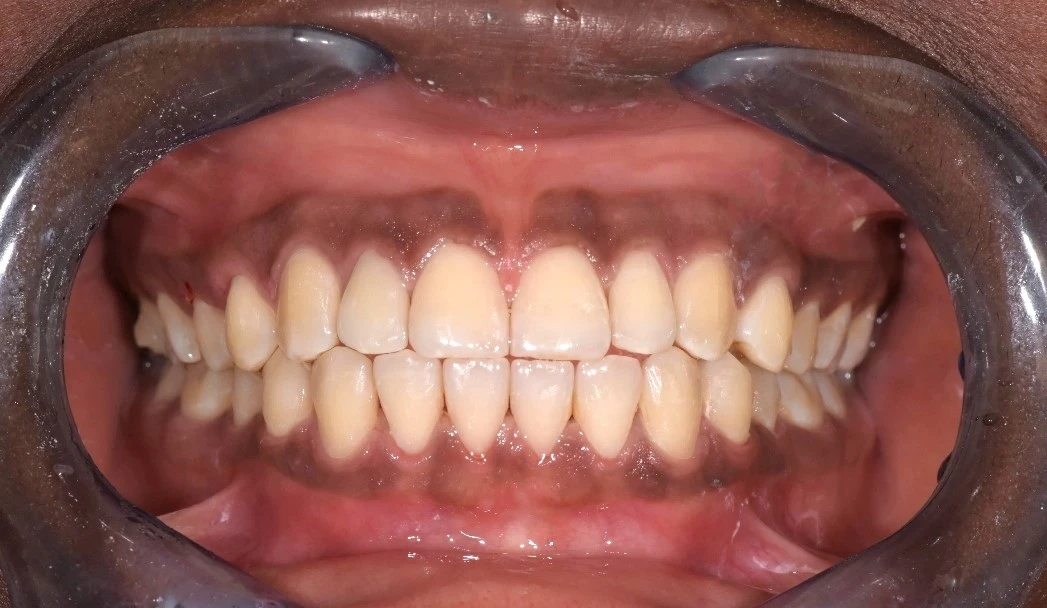

Orthodontie chez l'adulte

De nos jours, les adultes ont de plus en plus souvent recours aux traitements d’orthodontie, du fait de la déstigmatisation de l’orthodontie, « autrefois réservée aux adolescents », et de l’évolution des techniques, toujours plus discrètes.

Même si la croissance des mâchoires est terminée, il est tout à fait possible d’entreprendre une correction orthodontique à l’âge adulte, lorsque la santé des gencives et de l’os l’autorise.

L’aspect esthétique est très important pour le patient adulte : il constitue le motif de consultation le plus récurrent.

L’aspect fonctionnel, notamment incarné par les problèmes d’occlusion, représente tout de même une part non négligeable.

Sourire esthétique, discrétion des appareils et temps de traitement les plus courts possible : autant de demandes auxquelles nous pouvons répondre au sein du Cabinet dentaire de Seilh, grâce aux évolutions les plus récentes de la médecine dentaire. L’orthodontie numérique, entre autres, nous permet de planifier au mieux le résultat idéal pour chaque patient, qu’il s’agisse de traitements par gouttières Invisalign ou multi-attaches linguales.

Grâce à notre expérience et à nos compétences en analyse pluridisciplinaire, nous pouvons offrir à nos patients des résultats époustouflants et un confort incroyable, en corrigeant simultanément les aspects esthétiques et fonctionnels.

Ces techniques sont donc très efficaces et nos traitements d’orthodontie, associés aux méthodes de la dentisterie esthétique adhésive, garantissent des résultats optimaux, conformes aux attentes des patients.